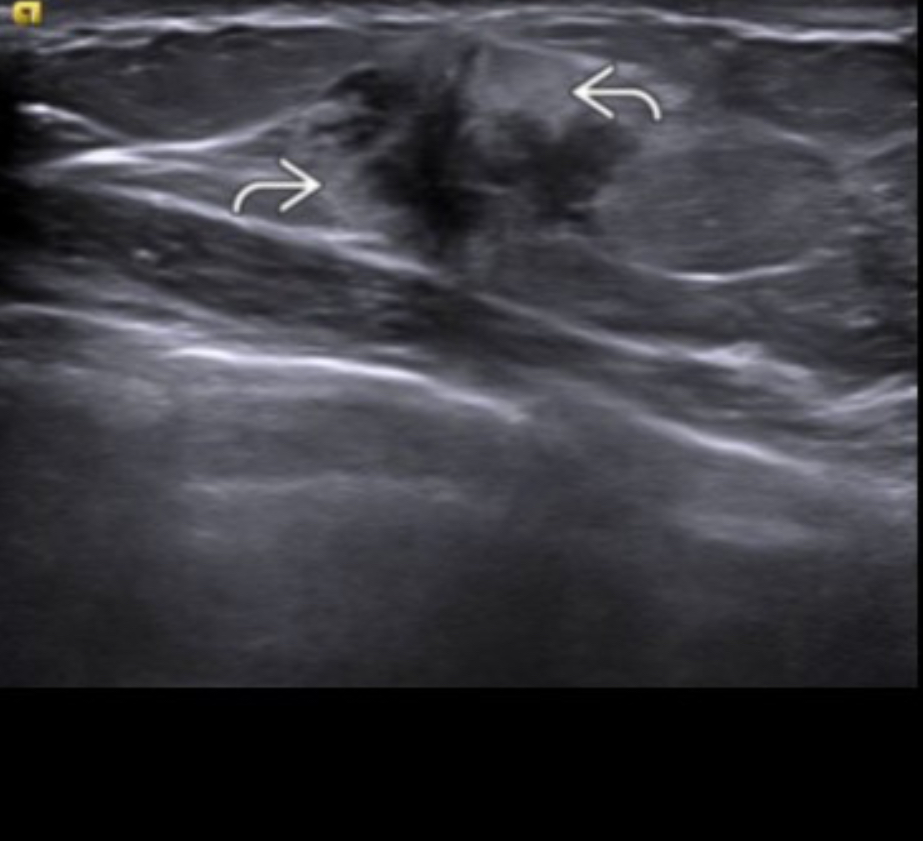

What is the echogenic halo secondary to?

Unresolved speculation and/or tumoral edema

Abrupt margins more likely to be benign

echogenic halo more likely to reflect malignancy (around70%)

(or wide transition zone)